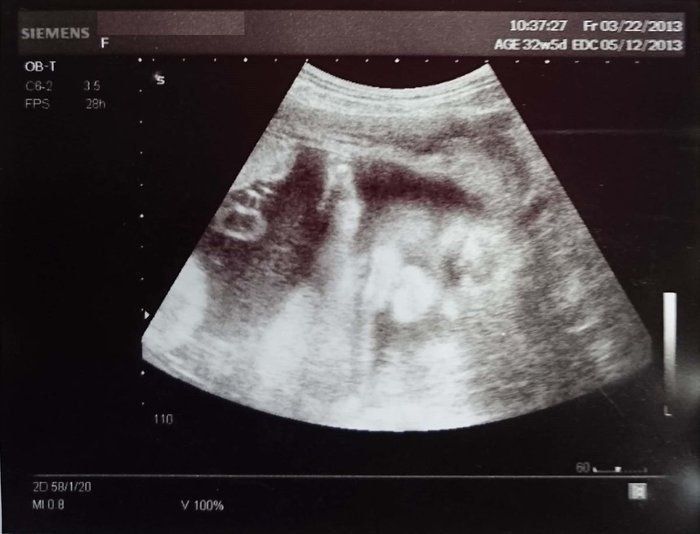

水野谷つむぎさんの妊娠32週目のエコー写真 赤ちゃんの推定体重2080g

この頃になると股関節痛が酷くなりました。少し歩いただけで、普通には歩けない状態になってしまい、道端でストレッチをしてしのいでいました。